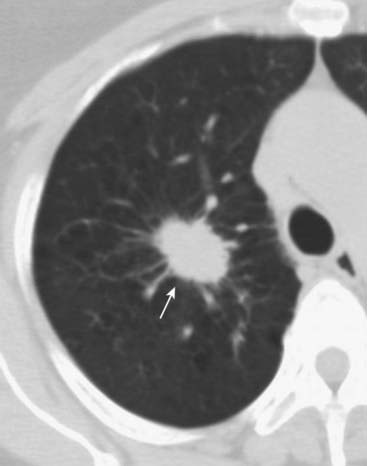

The hallmark lesion on CT is the signet-ring sign in which the bronchus, frequently with a thickened wall, becomes larger than its associated pulmonary artery; this is the opposite of the normal relationship between the two. The bronchus may also show a failure to taper normally (Fig. 12-29).

image

Figure 12-29 Bronchiectasis.

CT is the study of choice in diagnosing bronchiectasis. A, The hallmark lesion is the signet-ring sign in which the bronchus with a thickened wall (solid white arrow) becomes larger than its associated pulmonary artery (dotted white arrow); this is the opposite of the normal relationship between the two. B, The bronchus may also show tram-tracking, thickened walls, and a failure to taper normally (solid white arrows).